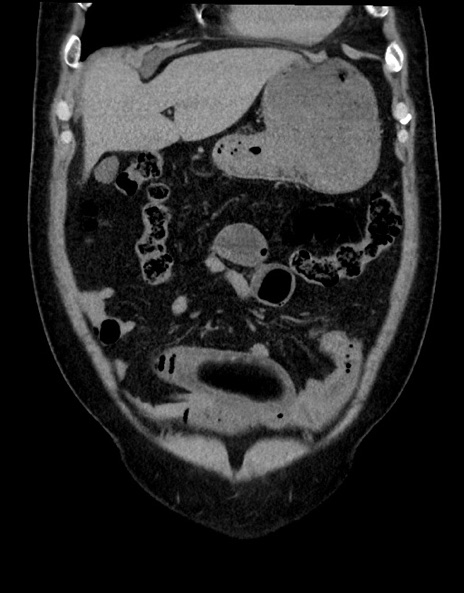

症例15(冠状断像)

【症例】70歳代男性

【主訴】腹痛

【現病歴】今朝から腹痛あり。全体的に痛い。特に左上の方。排ガスが今日はない。冷や汗が出る。

【既往歴】直腸癌術後

【身体所見】左側腹部〜上腹部に圧痛あり。腹膜刺激症状明らかなではない。軽度反跳痛。左下腹部に術後瘢痕あり。

【データ】WBC 7700、CRP 0.02